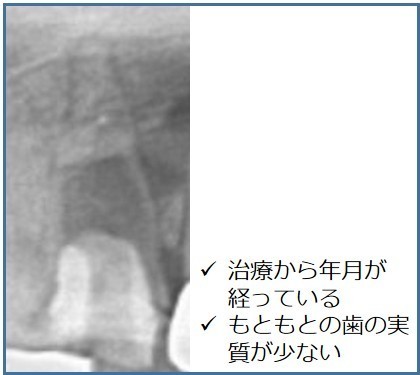

歯周病が中等度までであれば、適切な治療を行うことで歯を残せる可能性があります。しかし、歯槽骨が歯根の2/3以上吸収されてしまった重度の歯周病では、歯を保存することはできません。